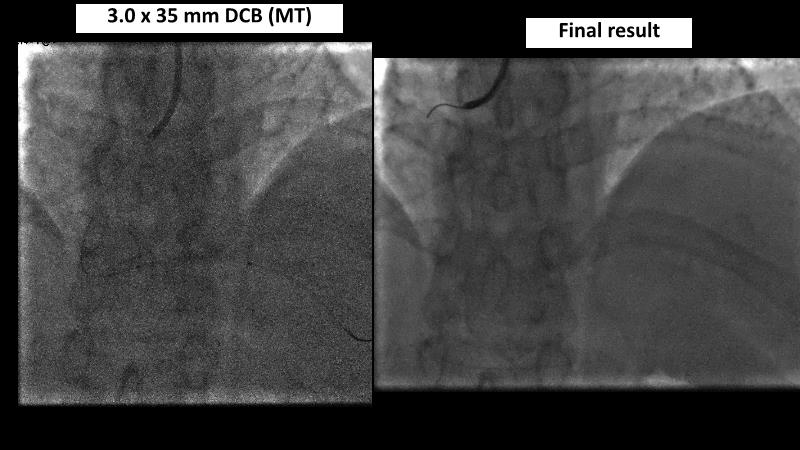

Watch this session to gain case-based insights on using DCBs in complex settings. Learn valuable tips and tricks for optimal DCB application, including the best timing and situations for their use. Discover how to effectively implement a hybrid strategy that combines DES and DCB when needed.

- To get a case based experience on how to use a DCB in complex settings

- To learn about tips and tricks on how and when to use a DCB: the ideal time and situation of DCB application in various complexities

- To utilise the hybrid strategy approach Combining DES and DCB when the situation demands